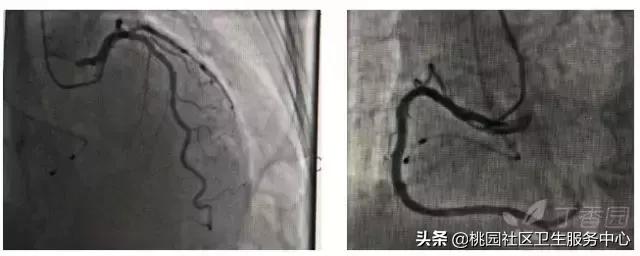

患者男性,54 岁,突发胸闷伴大汗 2 小时就诊,诊断:急性下壁心肌梗死(图 1)。入院 1 小时病情进展:室性逸搏或交界性逸搏伴右侧束支传导阻滞(图 2);入院 2 小时后突发心脏停搏抢救无效死亡(图 3)。

患者男,47 岁。血压高 20 余年,胸痛不适 1 年,再发 3 个月入院。A、B、C、D 图为同一时段不连续记录的动态心电图提示存在:T 波电交替(TWA)。诊断:变异型心绞痛。3 天后冠状动脉造影:前降支近段重度狭窄,对角支开口处重度狭窄,行 PCI 术好转。

A:*坐静**休息,窦性心律,ST-T 未见异常。

B:3 min 后,轻微闷痛,心电图 V3、V4 导联可见异常 J 波,V1~V5 导联 ST 段呈弓背型抬高伴 T 波直立高耸、ST-T 振幅呈高低交替。

C:35s 后,在 V1~V5 ST 段仍弓背抬高,第 4 个心搏为,出现室性早搏。

D:1 min 后,ST-T 已恢复正常。